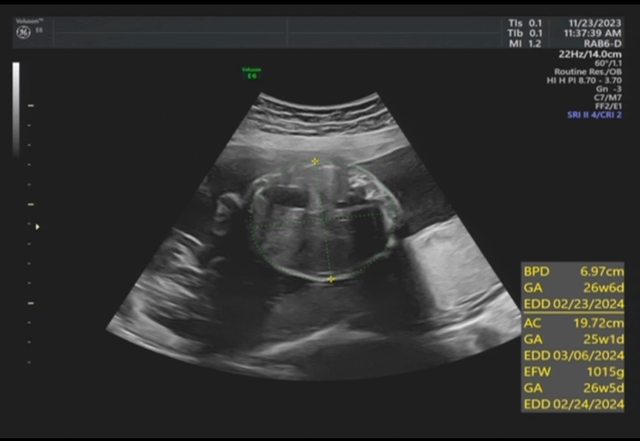

昨天去產檢,醫生覺得寶寶的胃偏大之後要注意觀察 我搜尋了一下好像只有看到胃太小的文,請問大家有沒有遇過類似情況? 我後來看了一下22週的高層次照片,那時候寶寶也是胃大大的,但那時只說是寶寶可能剛 吃飽 https://i.imgur.com/amlKp09.jpg

每一胎的狀況真的不一樣,這次第二胎先歷經羊水少週數小三週,到現在追到剩小一週, 但昨天醫生又提醒胃好像偏大,只希望二寶可以健康平安出生~ -- ※ 發信站: 批踢踢實業坊(www.ptt.org.tw), 來自: 101.12.24.40 (臺灣) ※ 文章網址: https://www.ptt.org.tw/BabyMother/M.1700797726.A.8D2